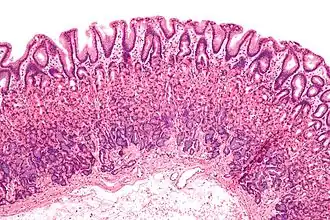

Mikroskopisch gesehen besteht der Magen aus:

- der Magenschleimhaut (Tunica mucosa gastrica), die aus den Laminae epithelialis, propria und muscularis mucosae besteht. Sie ist durch Einsenkungen (Foveolae gastricae) in zahlreiche Felder (Areae gastricae) gegliedert, mit einer Vielzahl von Drüsen (Glandulae gastricae).

- einer Bindegewebsschicht (Tela submucosa) mit Blutgefäßen

- einer Muskelschicht (Tunica muscularis gastrica) aus glatter Muskulatur, die aus den Fibrae obliquae, dem Stratum circulare und dem Stratum longitudinale besteht

- einem Überzug der Tunica serosa (Peritoneum)

Der Magen besitzt für die Sekretion von Hormonen und anderen Sekreten in seiner Schleimhaut verschiedene Zellarten, die an typischen Stellen des Magens lokalisiert sind, insbesondere

- in Korpus und Fundus: Nebenzellen (bilden Schleim), Hauptzellen (bilden Pepsinogen), Parietal- oder Belegzellen (bilden Salzsäure und Intrinsic Factor),

- im Antrum: G-Zellen (bilden Gastrin).